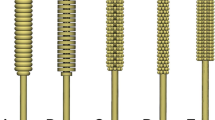

Traditional nasopharyngeal swabs are long and flexible, capable of being inserted into the nasopharyngeal space, with nylon flocking on the tip to enable sample collection. In appearance, the 3D printed swabs bear little resemblance to the traditional swabs (Figure 1). Some testing of the 3D printed swabs was conducted, most notably by the Veterans Health Administration (VHA)12 and Harvard University.1,13 The testing performed by the VHA compared the 3D printed and traditional swabs in actual use-case scenarios (e.g., ability to fit through the nasal cavity and reach the sampling location); however, some important usage scenarios were not evaluated (e.g., the ability of the swabs to be rotated at the sampling location). Additionally, several of the test protocols (i.e., mechanical testing) provide only qualitative assessments (e.g., asking users to assess prototypes’ mechanical properties such as breaking/bending rather than using a measurement tool) of their performance and allow for only a limited comparison among the different 3D printed (four prototypes) and traditional swabs.1,12,13 Additional quantitative assessments of some swabs (e.g., EnvisionTEC and Resolution Medical lattice swabs9,10) have been performed to compare their performance to traditional swabs; however, these studies do not allow for comparisons among other different 3D printed swabs. In this work, we present a framework for bench-testing nasopharyngeal swabs on mechanical and sample collection performance using standard and widely available material testing equipment. We aim to develop quantitative tests for nasopharyngeal swabs, covering the normal usage performance metrics, allowing for comparisons between the traditional and the newly manufactured, 3D printed swabs.

Both 3D printed and traditional nasopharyngeal swabs were tested (Table I, Figure 1) on mechanical performance, sample collection efficiency (uptake/release and viral RNA recovery), and other preclinical metrics (i.e., PCR compatibility, physical abrasion). The mechanical test protocols developed were designed to emulate the clinical use of the nasopharyngeal swabs and to evaluate the potential failure modes. The mechanical analysis included testing of the swabs in tension to mimic swab catching when pulled out of the nasopharyngeal space; torsion to mimic catching on an obstruction when being rotated within the nasopharyngeal space, and flexure to mimic bending when inserted into a nasal cavity. The effects of sterilization method and shelf-aging on mechanical performance were also evaluated. The sample collection efficiency, and other preclinical metrics, were designed to ensure the swabs collected sufficient sample to test for the presence of the virus, without causing injury to the patient (e.g., epistaxis). Abiogenix swabs were provided by Abiogenix for testing. Formlabs swabs were printed by the authors using Formlabs Form 3B Printer and Formlabs Surgical Guide Resin. All other swabs were purchased from their respective suppliers. The number of replicates (i.e., swabs) used for each test is noted. All swabs were sterilized before testing either by the manufacturer or by the authors following the manufacturer’s recommendations.